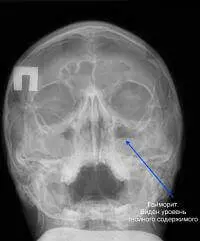

При діагностиці важливо знати, як виглядає рентгенівський знімок гаймориту. Цей метод обстеження не дозволяє побачити м’які тканини, але кісткові структури видно чітко. У випадку, якщо відтінки очних ямок і пазух носа на знімку ідентичні, це означає, що запалення немає. Гнійний вміст візуально є великими затемненими ділянками.

Патологія виникає внаслідок запалення гайморових пазух. Це буде добре помітно на затемнених ділянках носа та очних ямок. Одночасні процеси запалення в гайморових та лобових пазухах свідчать не тільки про гайморит, а й фронтит.

У кожному випадку гаймориту стан гратчастої кістки оцінюється фахівцем зі знімку носа. Часто інфільтративна рідина збирається у верхньощелепних пазухах. Рідина проявляється у вигляді ясно вираженої білої ділянки, яку легко помітити. Це явна ознака патології, яка є підставою для остаточного діагнозу.